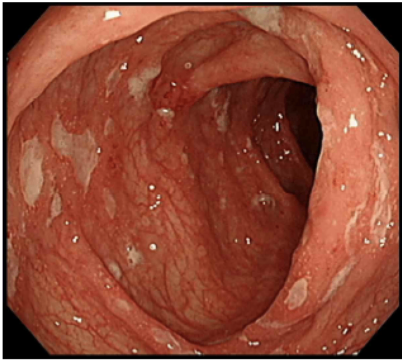

14세 남아가 4개월 전부터 배가 아프고 설사를 해서 병원에 왔다. 오른쪽 아랫배가 주로 아프고, 하루 4~6회의 검붉은 피가 섞인 설사를 한다고 한다. 수면 중에도 설사 때문에 잠을 설쳤다. 그동안 진통제와 지사제를 복용했지만 호전이 되지 않았다. 최근 1년간 체중이 7 kg 줄었다. 혈압 120/80 mmHg, 맥박 70회/분, 호흡 15회/분, 체온 37.2 ℃이다. 배 진찰에서 장음은 정상이고 오른쪽 아랫배에 압통이 있지만 덩이는 만져지지 않는다. 검사 결과는 다음과 같다. 대장내시경 사진과 생검 사진이다. 급성기 초회 치료는?

Colonoscopy: Aphthous ulcer, skip lesion

• 대장내시경상 비교적 깊지 않은 Apthous ulcerskipped lesion의 형태로 존재하는데, 이는 크론병에서 흔히 나타날 수 있는 내시경 소견이며, 추가적으로 조직검사상 non-caseating granuloma 또한 확인할 수 있다.